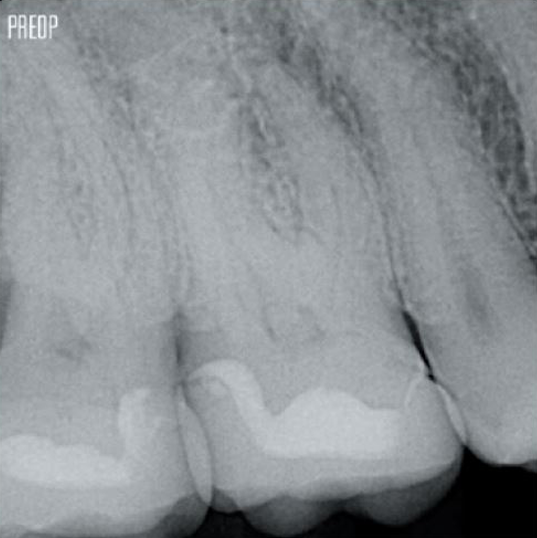

Photos courtesy of Dr. Ahmed Salman

More dentin preserved. Appropiate shaping, irrigation, and obturation ensured.

Retaining dentin serves as the critical base for a quality restoration following root canal treatment. The more dentin preserved during an endodontic treatment, the more options there will be to perform a successful, durable restoration.1

Successful root canal treatment starts with adequate access to the pulp chamber. The ideal procedure provides access to root canal orifices with minimal loss of dentin.